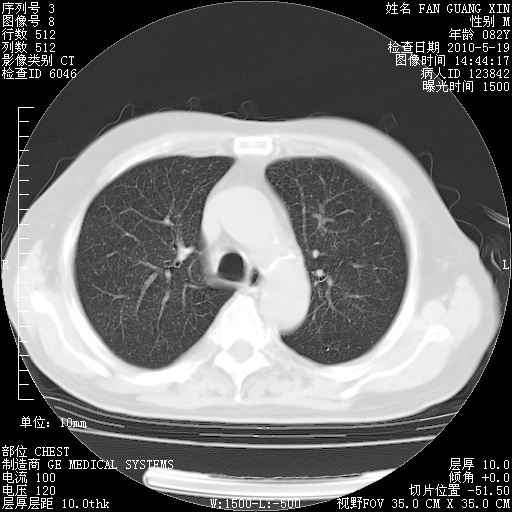

复查肺部CT,明显好转。为什么发热呢?

治疗3周后的肺部CT

治疗3周后的肺部CT纵隔窗